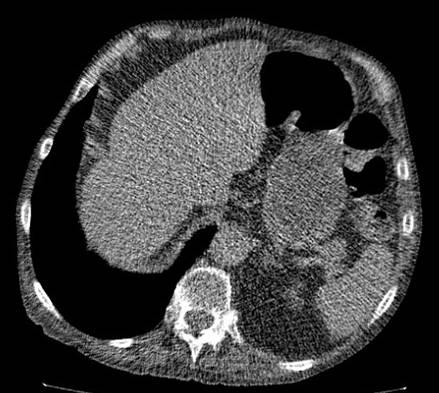

Thinner slice: higher noise

•Object ~ 5 mm

1mm